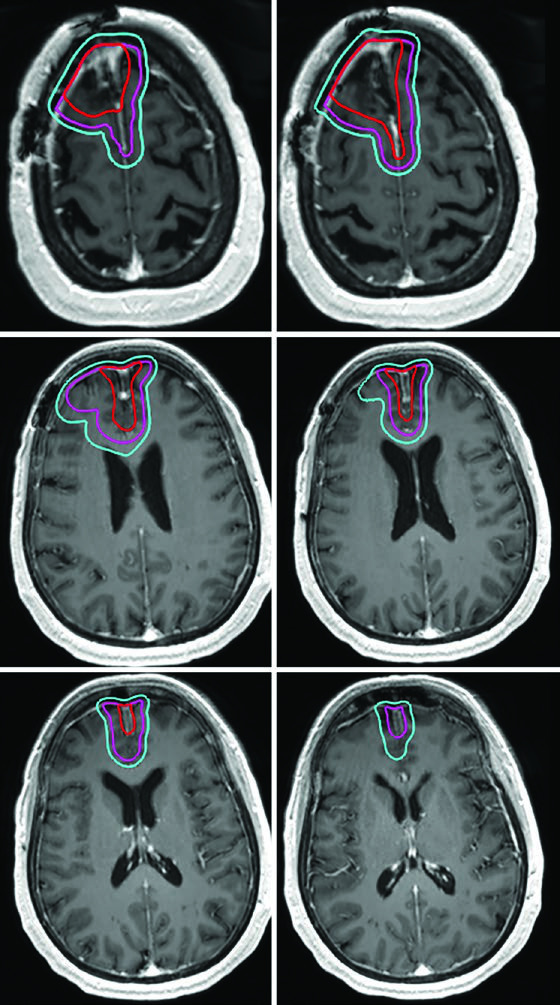

Glioma de Alto Grau: Volumes-Alvo e Fracionamento

Pacientes com astrocitoma de alto grau e oligodendroglioma passam por ressecção cirúrgica máxima para diagnóstico, caracterização molecular e citorredução. O tratamento padrão combina radioterapia conformacional fracionada com quimioterapia — seja concomitante, adjuvante ou ambas.

A dose padrão para gliomas de alto grau é de 59,4–60 Gy com fracionamento convencional. Para pacientes idosos, frágeis ou com performance status limitado, esquemas hipofracionados são uma alternativa validada: 40,05 Gy em 15 frações ou até 25 Gy em 5 frações, com margens reduzidas (0,5–1 cm). A tabela a seguir resume os volumes recomendados por tipo tumoral.

| Glioma anaplásico (captante) | Cone-down sequencial: PTV1 50,4 Gy (1,8 Gy/fx), PTV2 59,4 Gy (1,8 Gy/fx); ou SIB: PTV1 54,45 Gy (1,65 Gy/fx), PTV2 59,4 Gy (1,8 Gy/fx) | GTV1: volume T2/FLAIR; GTV2: cavidade pós-operatória + tumor residual na T1 pós-contraste | CTV1: 1,5 cm restrito anatomicamente; CTV2: 1,0 cm restrito | 0,3–0,5 cm |

| Glioma anaplásico (não captante) / Astrocitoma difuso IDH-wild type | PTV1: 59,4 Gy (1,8 Gy/fx) | GTV: cavidade pós-operatória + tumor residual em T2/FLAIR | CTV: 1,5 cm restrito anatomicamente | 0,3–0,5 cm |

Um ponto prático fundamental: as expansões anatomicamente restritas significam que o CTV não cruza a linha média, não invade a cisterna pré-pontina, não se estende pelo crânio e não ultrapassa o tentório para a fossa posterior. No entanto, tratos em risco para disseminação tumoral contralateral — como o joelho do corpo caloso — devem ser incluídos. Essa nuance aparece claramente nos casos de glioblastoma frontal em que o tumor se aproxima do corpo caloso.

Alguns erros recorrentes no planejamento de tumores malignos do SNC merecem destaque. O mais comum é aplicar expansões isotrópicas sem respeitar as barreiras anatômicas. O CTV de um glioblastoma frontal não deve cruzar a linha média — a menos que o joelho do corpo caloso esteja em risco, caso em que essa estrutura deve ser explicitamente incluída. Outro erro é ignorar a diferença entre as sequências de RM: o GTV1 deve ser baseado no FLAIR (edema perilesional), enquanto o GTV2 usa a T1 pós-contraste (doença captante residual).